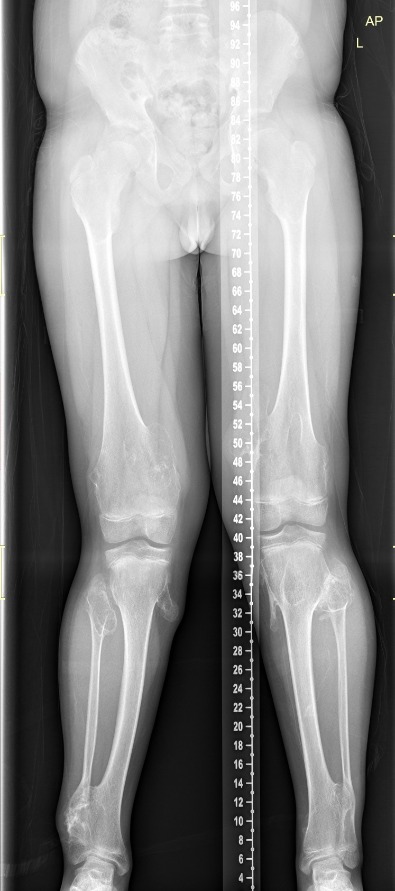

Οι εικόνες απεικονίζουν ένα περιστατικό με την Νόσο του Όλιερ, όπου παρουσίαζε κοντύτερο αριστερό άκρο. Χειρουργήθηκε από τον Δρ. Ζένιο με την χρήση εξωτερικής οστεοσύνθεσης.

Προ-εγχειρητικά

Εξωτερική οστεοσύνθεση

Μετ-εγχειρητικά